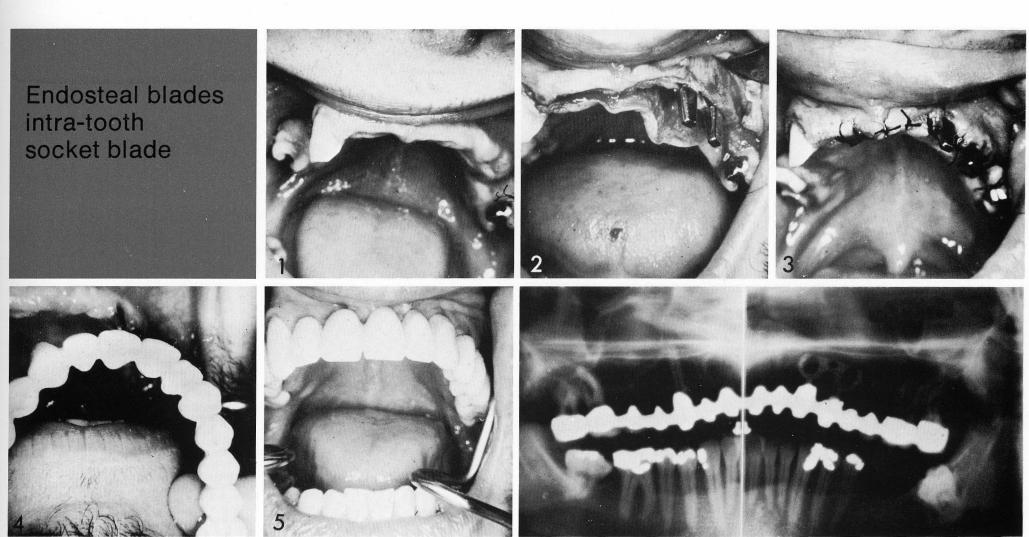

Endosteal blade

intra-tooth socket blade

1 Maxillary double posted bladevent implant used in a single site